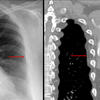

Aortic nipple

Ex 1 CT

Date: 03/23/2004

Views: 5362